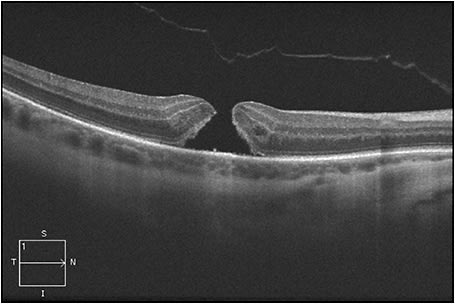

Figure 1 shows an eye in this series, with FTMH measuring 216 µm and concurrent focal VMT; this patient’s best-corrected Snellen VA was 20/70. Figure 2 shows VMT release following intravitreal ocriplasmin, with a decrease in VA to 20/200 at one week following injection. Figure 3 demonstrates an increase in FTMH size (now measuring 264 µm) at 12 days following injection.

Figure 1. An eye from the series at the New England Eye Center, with FTMH measuring 216 µm and concurrent focal VMT; this patient’s best-corrected Snellen visual acuity was 20/70.